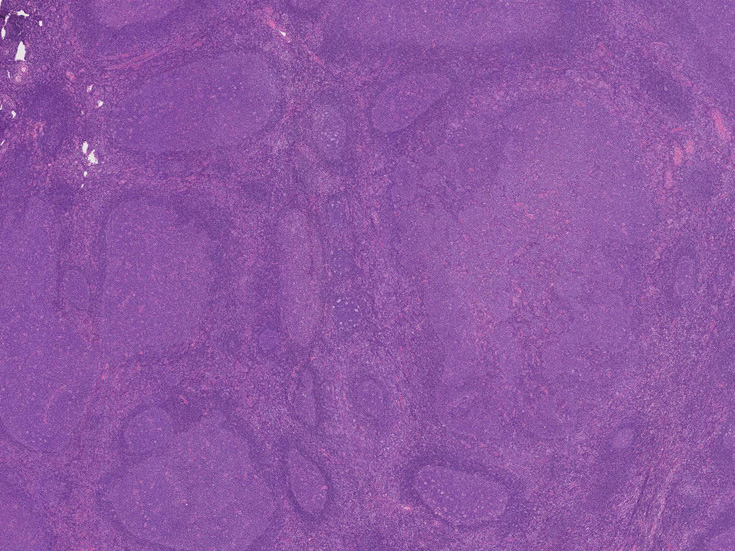

大きな胚中心を持つ多数のリンパ濾胞が見られる。胚中心の辺縁は不明瞭でマントル層も薄くなっている。1カ所マントル層リンパ球の侵入によりバラバラになった巨大な胚中心が認められ, macrofollicular patternと記載されるPTGCです。

鑑別にあがるfollicular lymphoma floral variantは全ての濾胞が腫瘍性であり, 本性例では除外可能と考える。

Diagnosis: Reactive lymphadenitis with PTGC